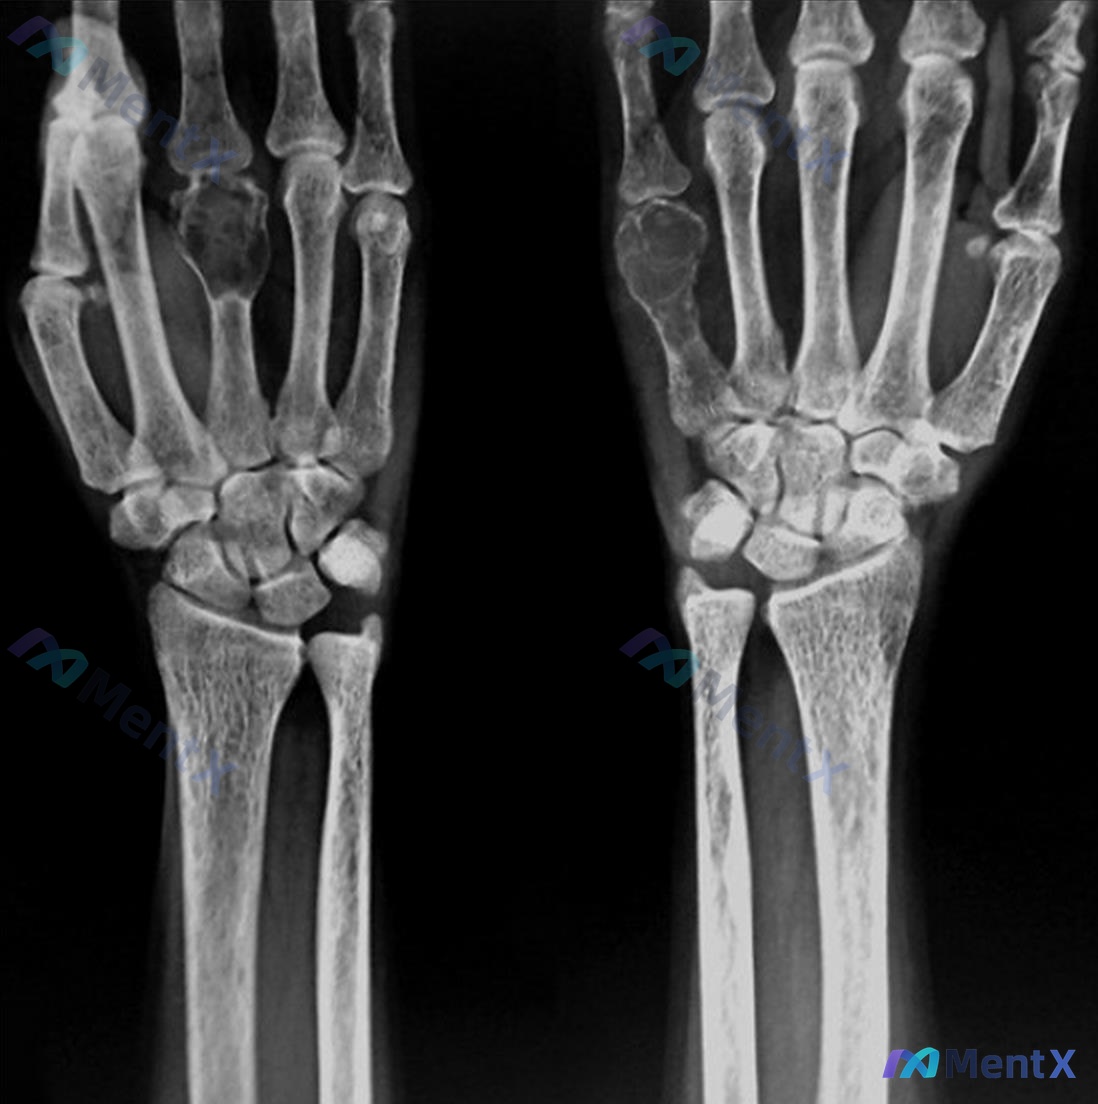

- 手腕 X 光:双侧手部及腕部骨密度普遍减低,多个掌骨及指骨可见边缘清晰的溶骨性透亮影,呈多发性膨胀性改变。